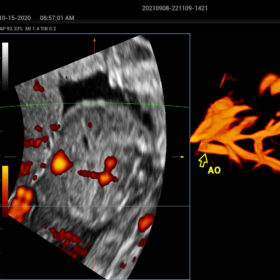

The ZST+ platform is a remarkable advancement, marking a significant evolution in ultrasound technology. It revolutionizes the processing of ultrasound metrics, moving away from the traditional beam-forming approach to channel data-based processing. This breakthrough eliminates the longstanding trade-off challenges between spatial resolution, temporal resolution, and tissue uniformity. The result is outstanding image quality, providing limitless imaging solutions with continuous enhancements.

- Smart HRI– Automatic regognition of liver and renal cortex and brightness ratio calculation

- HD-Scope – improving diagnostic confidence of minor lessions

- Dehaze-improving image contrast resolution with deep presentation

- HR-Flow Improving the hemodynamic presentation